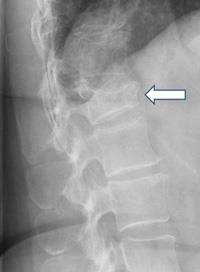

A vertebral compression fracture

A vertebral compression fracture (arrow) has a wedged-shaped appearance. The front of the vertebra has cracked and shortened while the back remains intact.